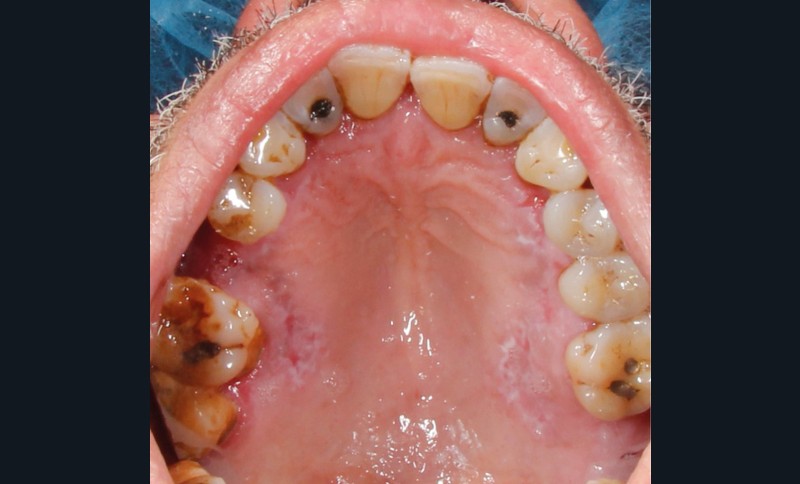

À l’interrogatoire, le patient affirme qu’il a des difficultés à maintenir une hygiène bucco-dentaire satisfaisante du fait des douleurs, et n’a pas pu consulter son chirurgien-dentiste pour son détartrage annuel en raison de la crise sanitaire en cours. L’examen clinique révèle une parodontite chronique (stade 3) généralisée et des lésions jugales (fig. 1 et 2), labiales (fig. 3) et gingivales (fig. 4) érythémateuses et kératosiques. Les lésions kératosiques jugales sont de type réticulé (fig. 1 et 2) ; les lésions kératosiques labiales sont associées à de petites érosions (fig. 3) ; les lésions palatines à des ulcérations (fig. 5). La langue présente une lésion blanche en « tache de bougie » (fig. 6) ; la muqueuse du plancher buccale est saine (fig. 7). Le signe de la pince est négatif. Le patient n’est pas porteur de prothèse dentaire malgré un édentement de moyenne étendue. Aucune lésion cutanée ou génitale n’est rapportée par le patient.